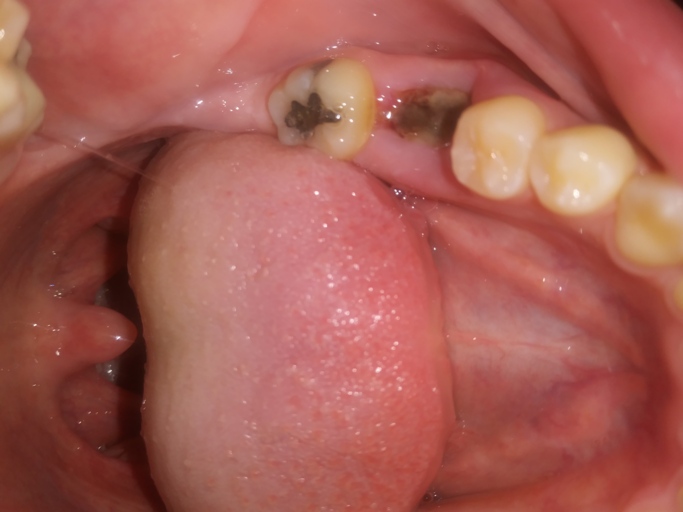

Wisdom teeth removed, is this dry socket or healing normally?

I’m concerned I have a dry socket from my salt rinses. Does this look like normal healing or is something wrong? It has a gray color and on the right side I can see some white. I got my teeth removed on 5/3 and felt like I was healing alright. I got...